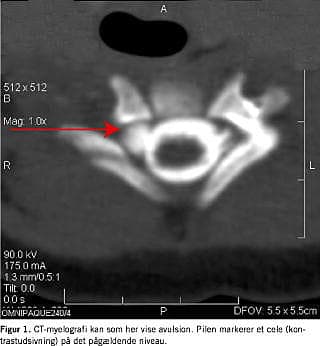

Det kliniske billede vil udvikle sig meget varieret i løbet af de første måneder, og mange pareser vil forsvinde i dette stadie [7]. Der vil dog være mange patienter, som ikke restitueres fuldt, således fandt Wickstrom et al, at kun 10% af børnene med komplette læsioner opnåede en brugbar funktion af armen [8]. Disse patienter skal reevalueres klinisk 3 mdr. gamle, og der suppleres eventuelt med elektromyografi og CT-myelografi (Figur 1). Der bør altid straks indledes fysioterapi for at modvirke kontrakturer (specielt indadrotationskontrakturer i skulderen) af fungerende muskler og ledkapsel, mens man afventer spontan bedring. På dette stadie vil en komplet parese med tilstedeværende Horners syndrom forblive uændret, og der bør planlægges tidlig operation i tremånedersalderen.

Myelografi er meget anvendt. Ordinær myelografi (under anvendelse af konventionel røntgen-teknik) giver mange falsk negative og falsk positive resultater. I dag er mængden af disse minimeret ved den mere sofistikerede CT-myelografi.

Der findes i det store og hele to patientkategorier: 1) Store nyfødte med høj fødselsvægt (ofte over 4 kg) i hovedstilling og med skulderdystoci. Det kræver stor trækkraft (ikke sjældent med anvendelse af tang eller kop) at forløse barnet. Dette resulterer i skade på øverste del af plexus brachialis, som regel C5 og C6, af og til også C7. Aldrig de nedre nerverødder (C8 og T1) (Figur 1 ), 2) underkropspræsentation af små (ofte under 3 kg) nyfødte, som kræver kraftig ekstention af hovedet og ikke sjældent manipulation af hånd og arm, medførende træk på både øvre og nedre nerverødder. Dette kan forårsage avulsion af en hvilken som helst eller i sjældne tilfælde alle nerverødder til plexus brachialis (Figur 2 ).